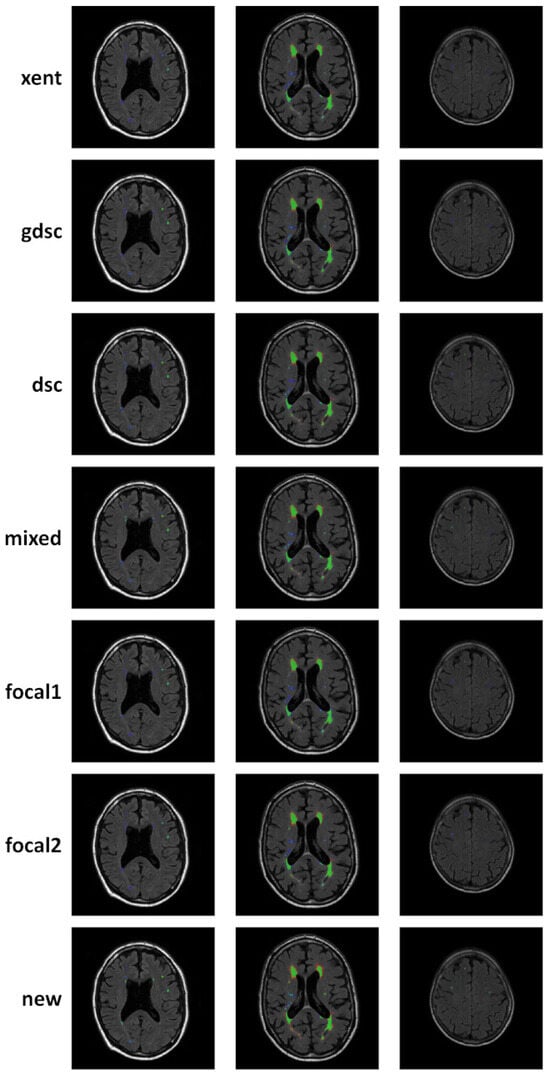

| xent | 0.64 | 0.51 | 0.46 | 0.62 | 0.55 | 0.49 | 0.54 | 0.48 | 0.46 |

| gdsc | 0.93 | 0.54 | 0.53 | 0.96 | 0.81 | 0.77 | 0.82 | 0.20 | 0.29 |

| dsc | 0.96 | 0.55 | 0.52 | 0.99 | 0.89 | 0.84 | 0.54 | 0.29 | 0.24 |

| mixed | 0.93 | 0.55 | 0.54 | 0.98 | 0.86 | 0.82 | 0.74 | 0.18 | 0.24 |

| focal1 | 0.59 | 0.48 | 0.46 | 0.52 | 0.49 | 0.49 | 0.55 | 0.53 | 0.49 |

| focal2 | 0.89 | 0.60 | 0.56 | 0.97 | 0.70 | 0.63 | 0.78 | 0.48 | 0.38 |

| new | 0.79 | 0.58 | 0.56 | 1.00 | 0.94 | 0.90 | 0.36 | 0.14 | 0.23 |